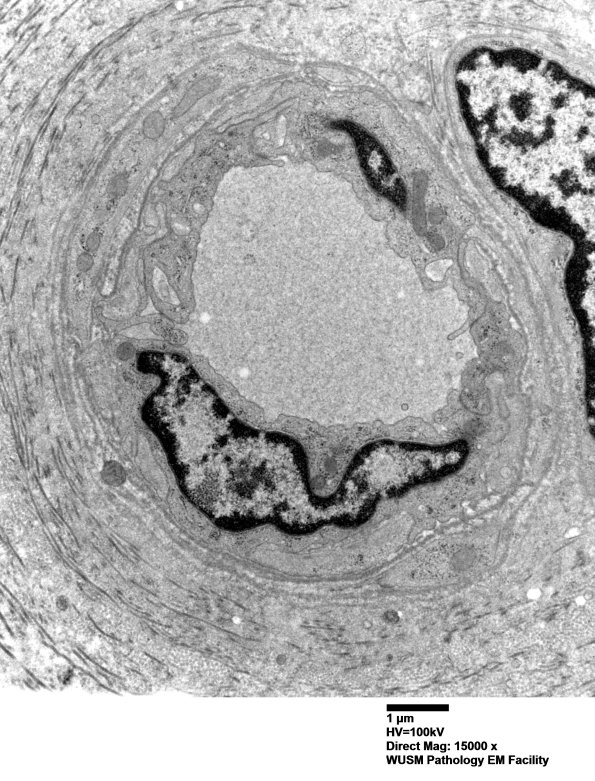

Washington University Experience | VASCULAR | Hypoxia-Ischemia, fetal-neonatal | White Matter | 17B2 (Case 17) HIEM EM016 - Copy

17B2 (Case 17) HIEM EM016 - Copy